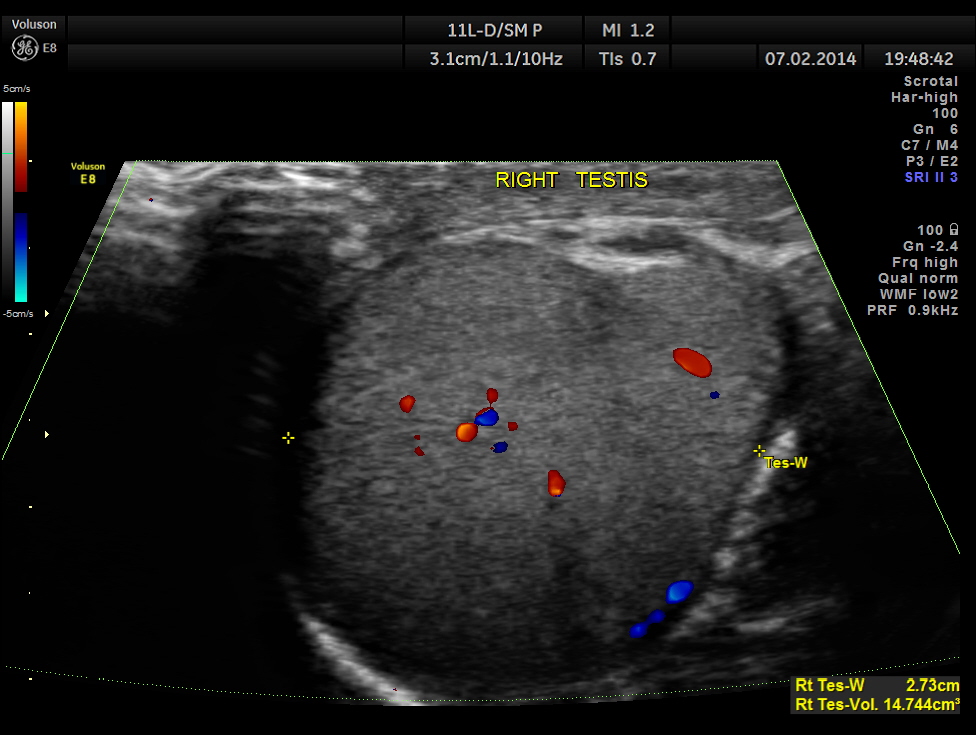

The following pictures show the testicles.Mild left hydrocele is also seen.

This patient had bilateral varicocele , left side being more prominent. Mild left hydrocele was also present.